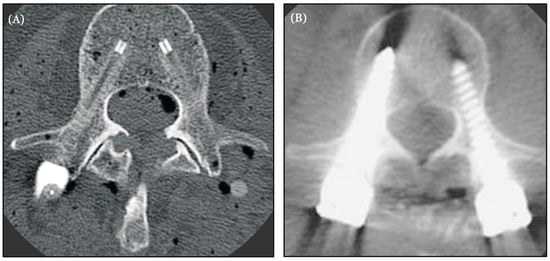

- Krätzig, T.; Mende, K.C.; Mohme, M.; Kniep, H.; Dreimann, M.; Stangenberg, M.; Westphal, M.; Gauer, T.; Eicker, S.O. Carbon fiber-reinforced PEEK versus titanium implants: An in vitro comparison of susceptibility artifacts in CT and MR imaging. Neurosurg. Rev. 2021, 44, 2163–2170. [Google Scholar] [CrossRef] [PubMed] [PubMed Central]

- Hubertus, V.; Wessels, L.; Früh, A.; Tkatschenko, D.; Nulis, I.; Bohner, G.; Prinz, V.; Onken, J.; Czabanka, M.; Vajkoczy, P.; et al. Navigation accuracy and assessability of carbon fiber-reinforced PEEK instrumentation with multimodal intraoperative imaging in spinal oncology. Sci. Rep. 2022, 12, 15816. [Google Scholar] [CrossRef] [PubMed] [PubMed Central]

| Imaging Compatibility | Safe MRI magnetic field. Does not cause artifact on CT | Safe on MRI magnetic field. Some artifact on CT | Incompatible with MRI imaging. Significant artifact on CT |

| Hubertus et al. (2022) | Carbon fiber reinforced PEEK (CFR-PEEK) | Evaluation of the performance and precision of 3D intraoperative imaging and navigation systems in thoraco-lumbar instrumentation with CFR-PEEK pedicle screws | Navigation accuracy was considerably lower for CFR-PEEK pedicle screws than reported for titanium implants. CT may be the best imaging modality for CFR-PEEK instrumentation assessment [55] | N |